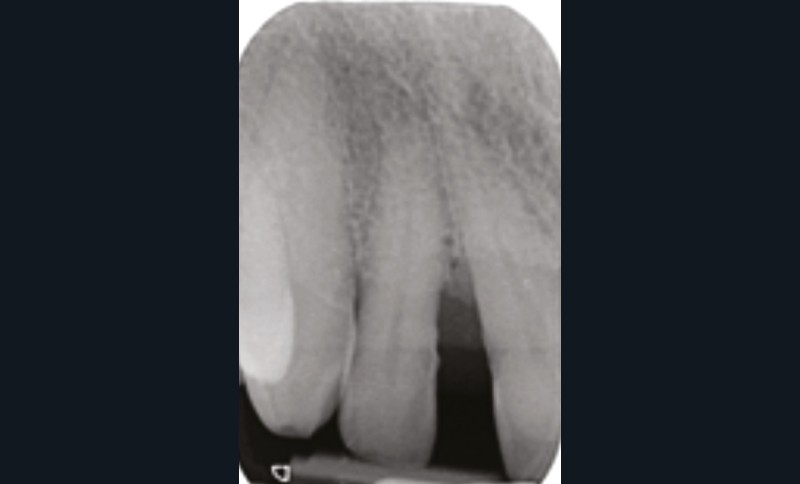

La migration dentaire pathologique est un déplacement dentaire provoqué lorsque l’équilibre entre les forces qui maintiennent la position physiologique de la dent et les forces qui tendent à la déplacer est rompu [1]. Selon la quantité de perte d’attache, de simples forces occlusales ou la poussée linguale lors de la déglutition suffisent à déplacer la dent.

L’étiologie des MDP est complexe et souvent multifactorielle. L’inflammation du parodonte (et son élargissement desmodontal), mais surtout la perte du ligament et de l’os alvéolaire dans lequel il est attaché, diminuent la solidité de l’ancrage et la résistance de la dent à l’impact des forces en présence :

- occlusion naturelle ou traumatique (perte de dents avec ou sans effondrement occlusal postérieur, interférences occlusales) ;

- parafonctions (bruxisme, clenching, déglutition atypique…) ;

- fonctions orales : phonation, mastication, déglutition (pression exercée par la langue, les lèvres, les joues…) ;